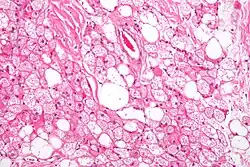

Hnědý adipocyt je buňka obsahující v cytoplazmě mnoho drobných tukových kapének (na rozdíl od běžného bílého adipocytu s jednou velkou kapénkou). Soubor těchto buněk pak tvoří hnědou neboli multilokulární tukovou tkáň. Za hnědou barvu je zodpovědný cytochrom, který je ve velkém množství obsažen v mitochondriích těchto buněk. Jádro každé hnědé tukové buňky je v její cytoplazmě náhodně umístěno, na rozdíl od bílého tuku je však mohutnější a okolo něj se hromadí silně eozinofilní cytoplazmatická hmota.

Histologicky hnědá tuková tkáň připomíná endokrinní žlázu. Inervována je na rozdíl od bílé tukové tkáně přímo (sympatikem) a je také bohatě cévně zásobena. Cévy a nervy jsou pouze v přepážkách, oddělujících od sebe ostrůvky hnědých adipocytů.